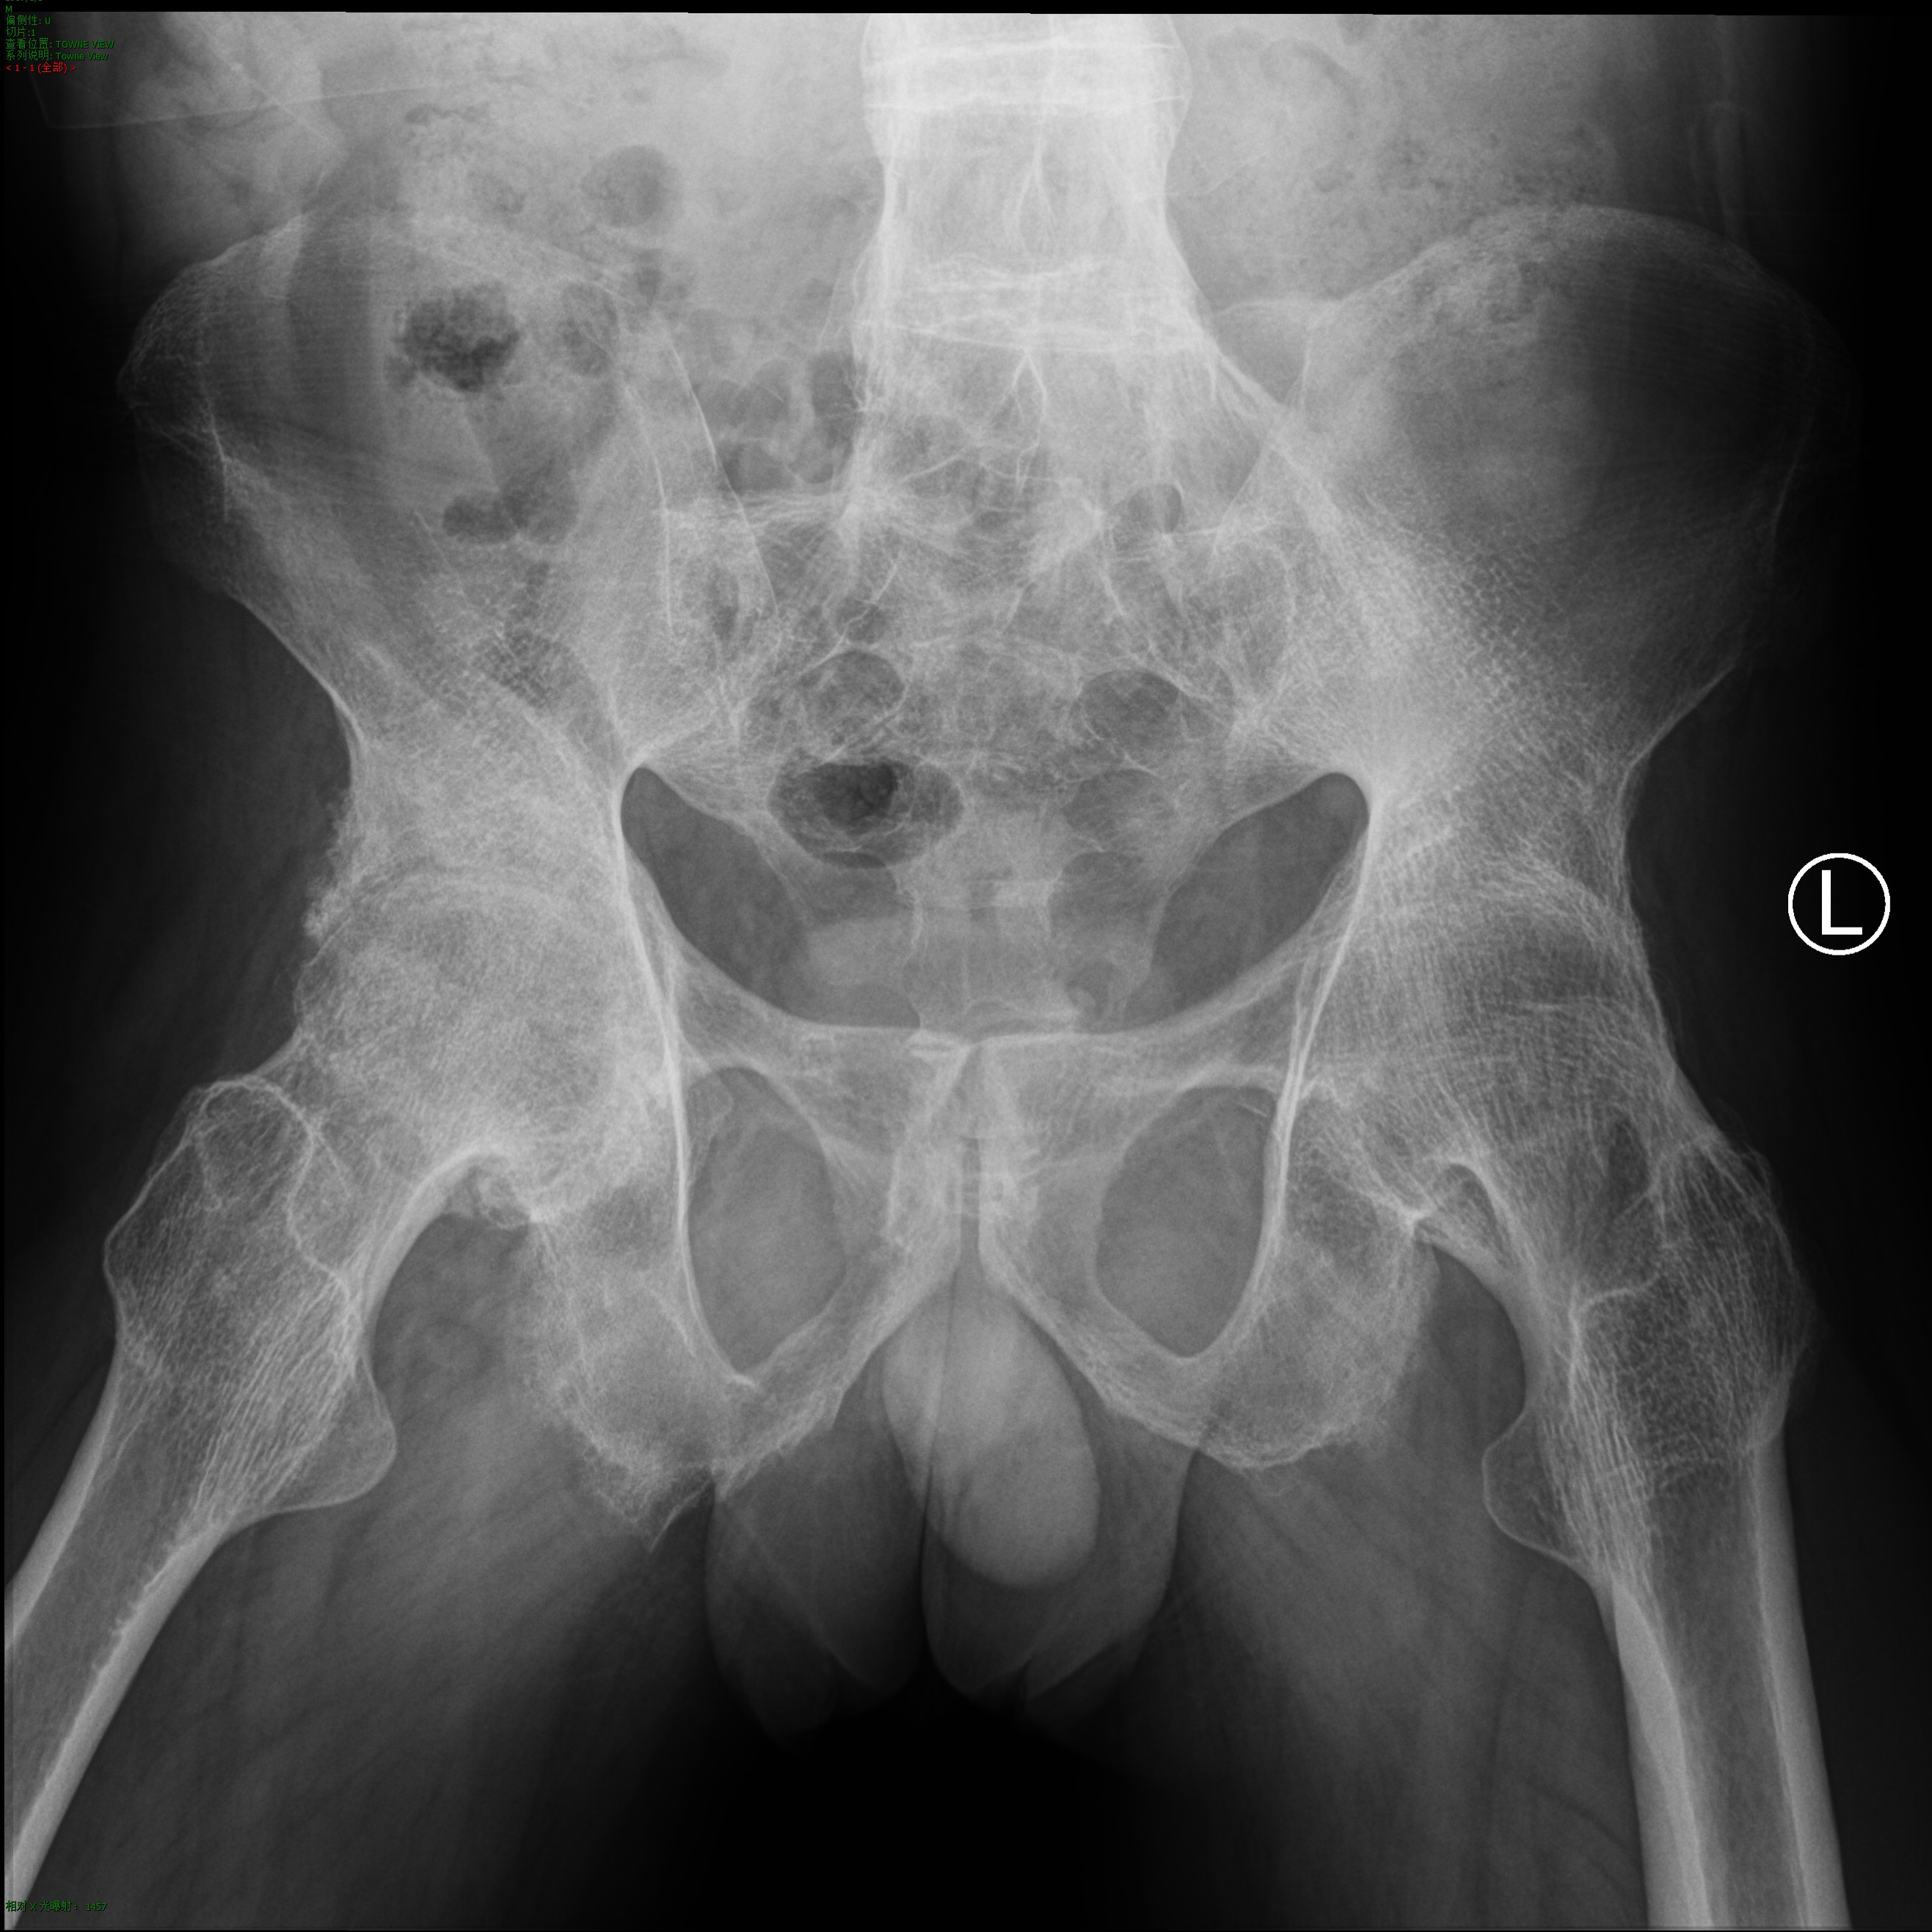

术后脊柱、髋关节影像

手术前(上)、后(下)对比